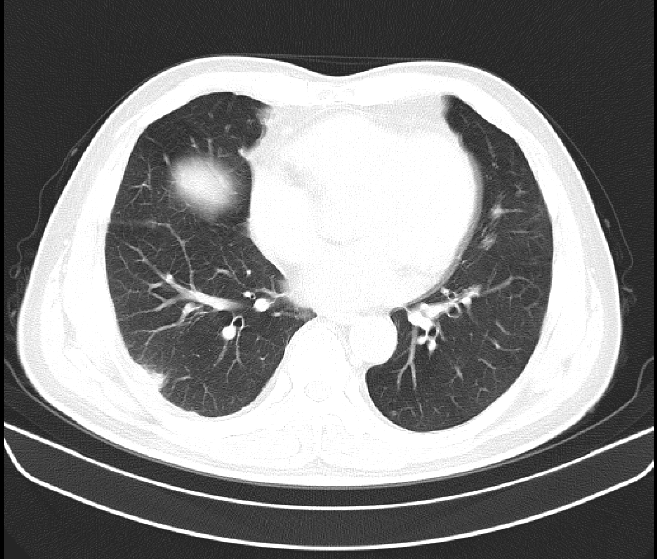

1.2차 아스트라 맞고 괜찮았는데 12/16일에 3차로 화이자 백신 맞고 다음날부터 아프기 시작하여 병원을 다니며 x-ray도 찍고 피검사도 하고 링겔도 맞고 5차례 주사 맞으며 약 먹으며 괜찮아지나 싶었는데 1/1일 20시경부터 흉통과 호흡곤란이 급격히 심해져 다니던 병원 응급실에서 CT와 각종검사결과 폐암의심 소견으로 바로 큰병원 응급실로 가서 격리실에서 통증으로 소리지르고 정신도 왔다갔다하는데 새벽에 의사 3명인가? 들어오더니 폐암이 의심된다 하더라구요~ㅠㅠ 그후 이틀간 금식하며 검사결과 상세불명의 급성폐렴,폐의농양으로 20여일간 입원후 퇴원하고 한달에 한번씩 CT찍으며 추적검사중인데 가슴이 뻐근하고 옆구리도 결리면서 호흡이 아직도 불편합니다. 주변에서는 폐는 회복이 안된다고 많이 얘기하니 답답하네요~ 병원비에 시간도 그렇고 ㅠㅠ 1/1일 CT사진 입니다.

백신 접종과 그 후유증으로 폐손상은 연관성을 찾기가 어렵습니다. 처음에 폐암으로 의심되었던 병변은 폐렴 및 폐농양으로 확인이 되었다면 일반적으로 폐농양이 다발성이거나 크지 않다면 특별한 후유증을 남기는 경우는 흔치 않습니다. 현재 CT 상에서도 폐실질이 손상되는 코로나19 감염 후 ARDS 소견과는 거리가 있어 보입니다.

현재 보이는 RLL lung mass가 흉통의 원인인지는 알 수 없지만 충분히 Cancer의 가능성

이 있으며 이에 대해 조직 검사 등 Evaluation 이 필요한 것으로 보입니다.

흉통은 심장 등 협심증으로 인한 흉통의 가능성이 있으며 흡연을 하시는 경우 오른쪽 아래의

병변은 충분히 악성 종양의 가능성이 높아 조직 검사를 진행하는 것이 좋을 것으로 생각됩니다.